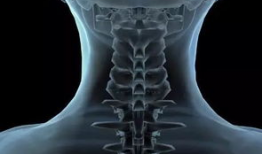

你是不是也和我一样,长时间对着电脑工作,感觉脖子酸酸的,颈椎不舒服呢?别担心,今天我要给你分享一组特别实用的颈椎保健动作,跟着我...